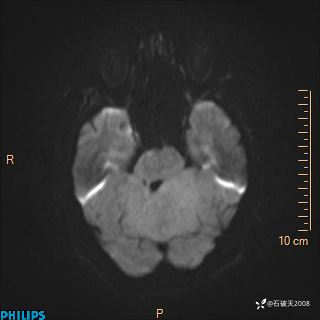

DWI